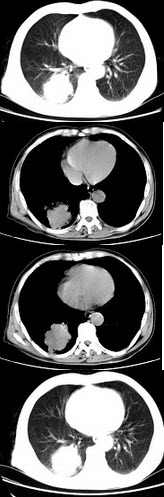

男,68岁,右侧胸痛伴右上臂麻木1周,胸部CT、MRI扫描如图,最可能的诊断为()

A.右上肺硬化性血管瘤

B.右上肺肉瘤并纵隔淋巴转移

C.右上肺不张

D.右上肺中央型肺癌并右上肺不张,纵隔淋巴转移

E.右上肺周围型肺癌并纵隔淋巴转移